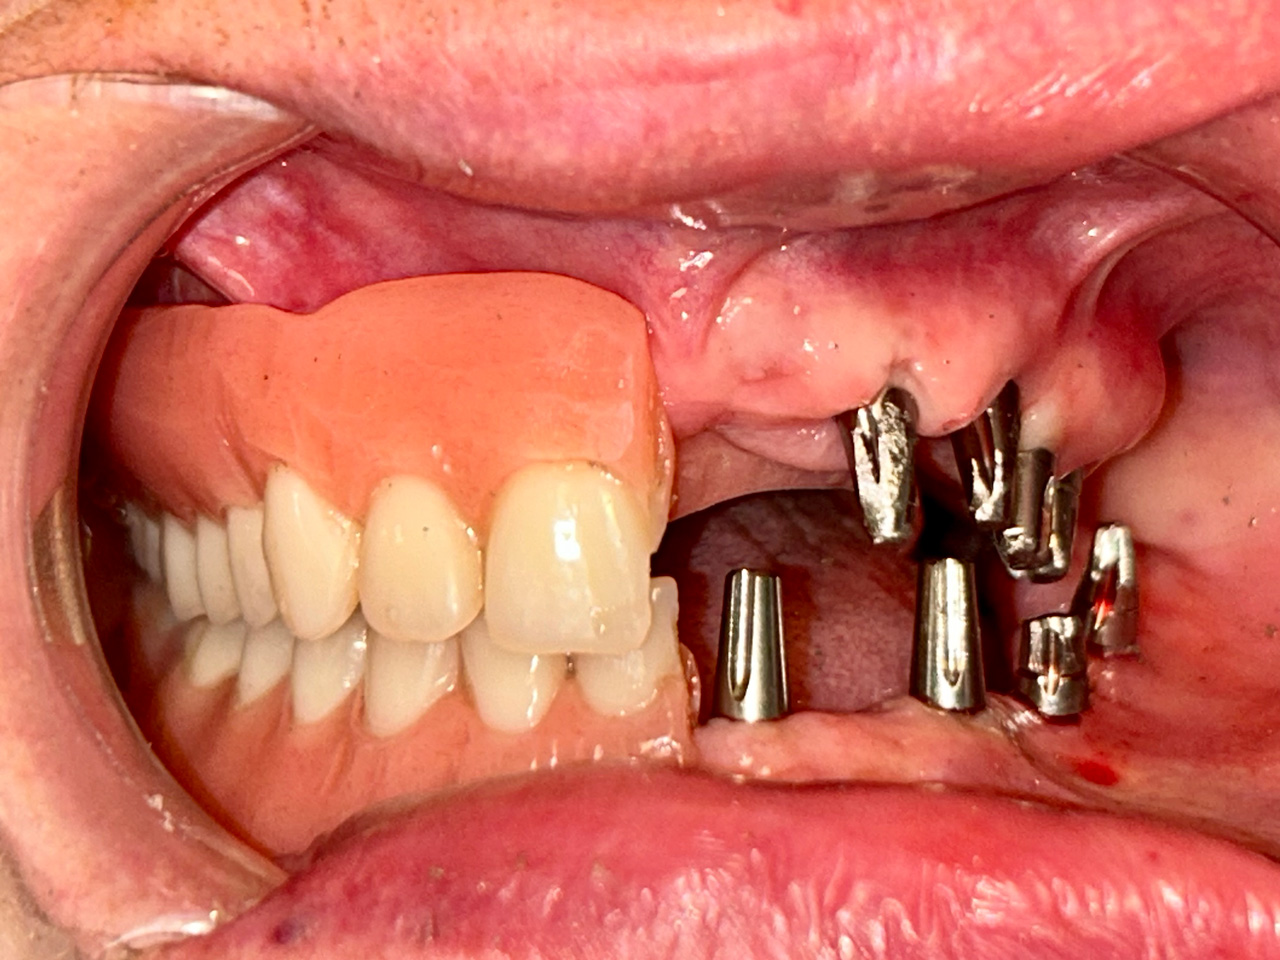

Elhanyagolt fogsor cseréje 2 nap alatt

2 nap alatt varázsoltuk ezt a szép esztétikus alsó, felső körhídat implantátumokkal megtámasztva a korábban elhanyagolt szájba. Az 1. nap 26 fogat távolítottunk el, mert annyira rossz állapotban voltak, és rögtön azonnal terhelhető IHDE svájci implantátumokat raktunk be, fentre 8, lentre 6 darabot. A sebeket összevarrtuk és intraorális szkennerrel digitális lenyomatot vettünk. 2 nap múlva pedig beragasztottuk a kész PMMA műanyag körhidakat. Dr. Kelemen Péter és a Symbion Fogtechnika munkája.